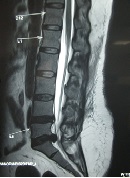

Correlation of Canal Dimension with Neurological Status and Surgical Outcome in Lumbar PIVD

Shafiq Hackla*, Farid Hussain Malik, Saumyjit Basu, Anil Kumar Gupta